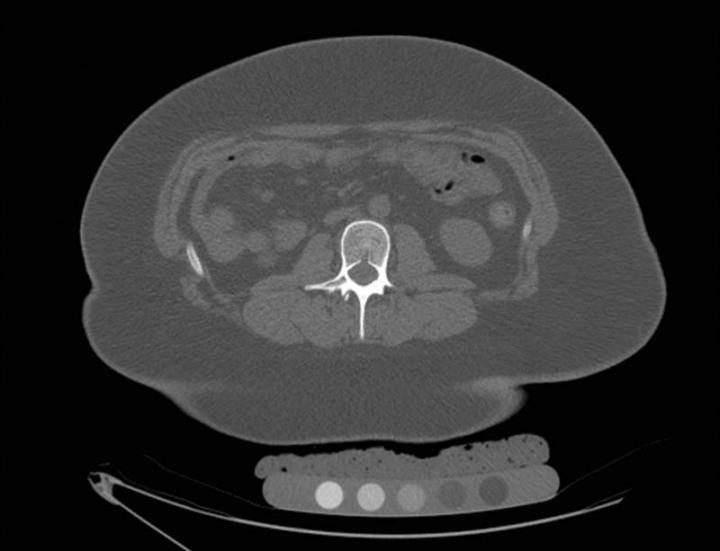

image: CT in a 17-year-old female prior to sleeve gastrectomy. Volumetric bone mineral density pre-surgery was 183 mg/cm3.

The study examined 52 adolescents with moderate to severe obesity, 26 of whom underwent sleeve gastrectomy. The other 26 were in the control group. Mean age was 17.5 years, and mean body mass index (BMI) was 45. BMI of 30 or above is considered obese. Thirty-eight of study participants were girls. Before and 12 months after sleeve gastrectomy (or no surgery), the patients underwent quantitative CT of the lumbar spine, to quantify volumetric bone mineral density. Quantitative CT is a highly accurate technique for detecting changes in volumetric bone mineral density after extreme weight loss.